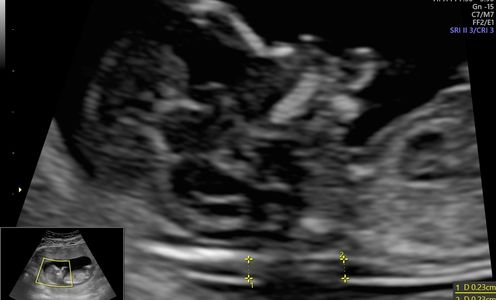

Estudio que se realiza entre la semana 20 y 30 de gestación; sirve para valorar crecimiento, órganos y estructuras de bebé. Se realiza para detectar malformaciones congénitas.